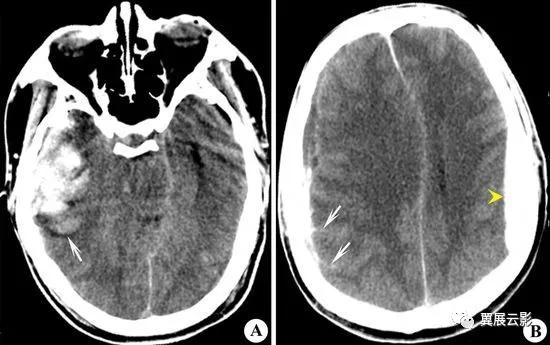

颅内出血

颅内出血在MRI检查中除具有CT的一般形态学表现外,主要表现为出血信号的不同,在出血信号方面,超急性期T1WI呈等或稍低信号,T2WI呈现高信号,T1WI呈现低信号或中心呈现低信号,周边高信号,T2WI呈现低或极低信号,亚急性期T1WI和T2WI均表现为周边高信号,中心低信号;慢性期T1WI和T2WI均为高信号,T2WI高信号周围可见含铁血黄素沉积的黑边;残腔期T1WI呈现低信号,T2WI呈现极低信号。脑出血周围水肿呈现长T1长T2信号,有一点需要说明,在疾病分类上大多数作者将硬膜下,硬膜外及蛛网膜下腔出血分在脑外伤中,本书之所以将这些疾病归入颅内出血一并讨论,主要考虑到各种颅内出血在MRI信号演变方面有共同规律。

病例1:脑出血(急性期)

脑出血重点应在诊断报告中写明出血的部位,大小或出血量,出血在T1WI和T2WI上信号特点,水肿情况及占位效应,鉴别诊断时应注意排除肿瘤卒中及脑血管畸形合并出血。

病例2:硬膜下血肿(亚急性期)

报告中重点描述硬膜下血肿的形态,信号,脑回推挤征及占位效应,诊断中应注意与硬膜外血肿相鉴别。

病例3:硬膜外血肿(超急性期)

书写报告时重点描述血肿的形态,部位,大小,信号及占位效应,鉴别诊断时重点与硬膜下血肿相鉴别。